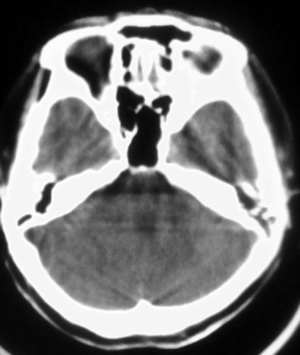

以下是引用拾荒者在2006-9-12 22:30:00的发言:[br]12楼战友说得极是,右侧侧脑室旁的低密度影性质?有增强的必要。